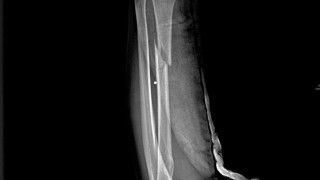

Potwierdzają to również liczne raporty składane przez żołnierzy rosyjskich sił zbrojnych. Wynika z nich, że to właśnie drony szturmowe stanowią obecnie największe zagrożenie nie tylko dla sprzętu wojskowego, ale i dla personelu. Rosyjscy medycy podkreślali przy tym, że większość ran spowodowanych przez bezzałogowe aparaty latające dotyczyła kończyn (około 58,2%) i według ich standardów były one kwalifikowane jako lekkie (73,3%). Do tego rodzaju wyjaśnień należy jednak podchodzić bardzo ostrożnie, ponieważ wytyczne rosyjskiego ministerstwa obrony wyraźnie nakazują, by unikać używania oceny „obrażenia ciężkie”, gdyż jest to związane z koniecznością wypłaty dużego odszkodowania.

Rosyjscy medycy wojskowi analizujący wyniki ankiety i badań doszli również do wniosku, że w wojnie okopowej wzrasta znaczenie zabezpieczenia osobistego (kamizelek kuloodpornych i hełmów). Dzięki niemu: w przypadku głowy obrażenia dotyczą nieosłoniętej części twarzy, a w przypadku klatki piersiowej – są to najczęściej siniaki i zamknięte złamania żeber.